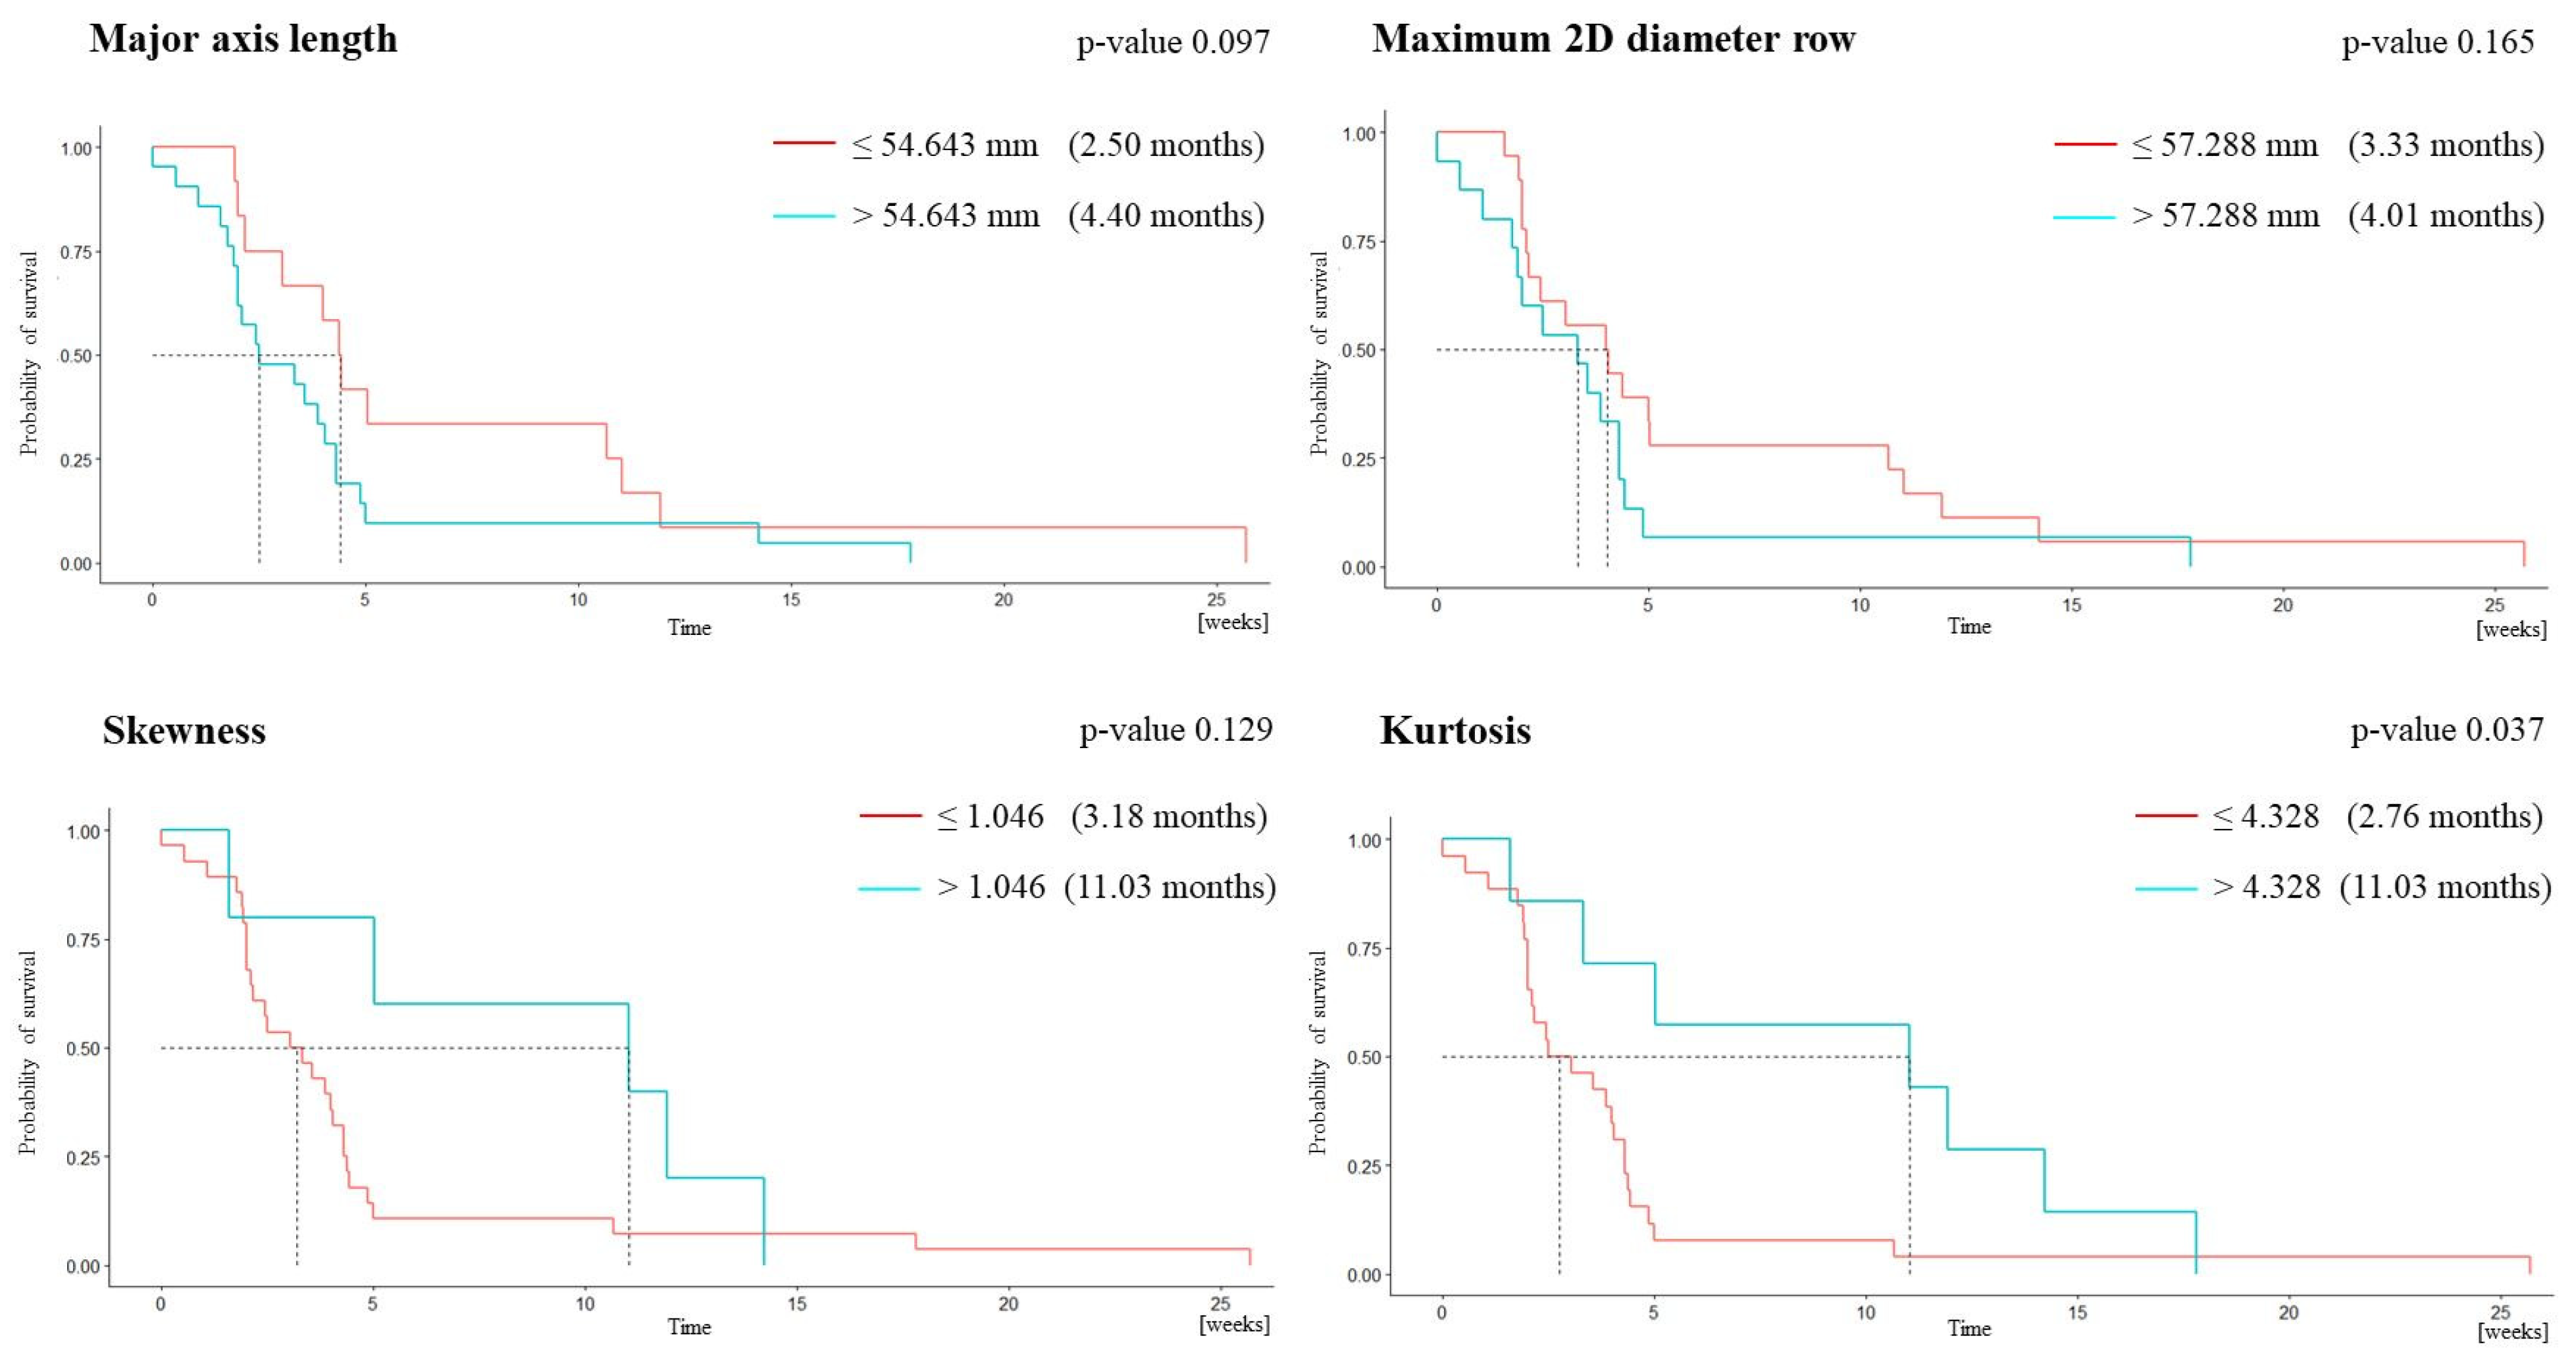

3.2. Survival Analysis

| Feature | Whole Cohort (n = 33) | PFS ≤ 6 Months (n = 27) | PFS > 6 Months (n = 6) | p-Value |

|---|---|---|---|---|

| MAL | 63.11 ± 21.11 | 66.46 ± 21.31 | 48.01 ± 12.54 | 0.027 |

| m2Ddr | 56.51 ± 17.82 | 59.07 ± 18.28 | 45 ± 10.03 | 0.021 |

| Skewness | 0.68 ± 0.46 | 0.60 ± 0.42 | 1.06 ± 0.48 | 0.021 |

| Kurtosis | 3.66 ± 1.89 | 3.36 ± 1.70 | 4.98 ± 2.30 | 0.035 |

| Univariate Analysis | ||||||

|---|---|---|---|---|---|---|

| Feature | AUC | Sensitivity | Specificity | PPV | NPV | Cut-Off Value |

| MAL | 0.790 | 0.667 | 0.704 | 0.333 | 0.905 | 54.643 |

| m2Ddr | 0.747 | 0.833 | 0.519 | 0.278 | 0.933 | 57.288 |

| Skewness | 0.802 | 0.500 | 0.926 | 0.6 | 0.893 | 1.046 |

| Kurtosis | 0.769 | 0.667 | 0.889 | 0.571 | 0.923 | 4.328 |

| Bivariate Analysis | ||||||

| MAL m2Ddr | 0.880 | 0.833 | 0.815 | 0.5 | 0.957 | 96.436 86.200 |

| MAL Skewness | 0.880 | 1.000 | 0.741 | 0.462 | 1.000 | 96.436 0.653 |

| Trivariate Analysis | ||||||

| MAL m2Ddr Skewness | 0.886 | 1.000 | 0.778 | 0.5 | 1.000 | |